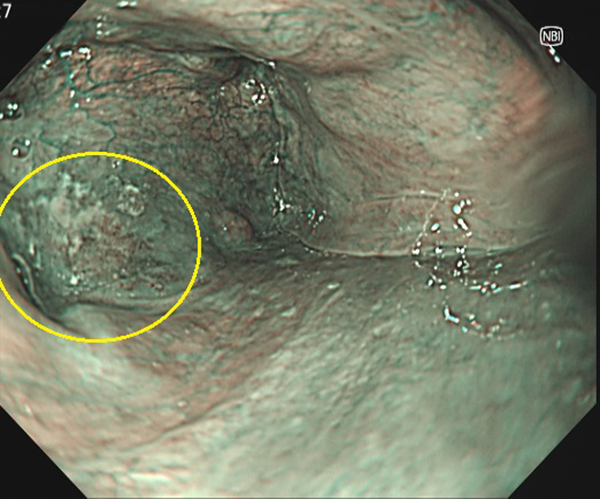

⑤大腸がん(側方発育型腫瘍(LST))

1. 大腸ポリープ既往歴があり、定期的検査として内視鏡検査を施行、横行結腸に10mm強の表面比較的平滑な扁平隆起を認めます。

2. NBI画像処理で表面構造の異常(周辺が均一な小円形構造に対し、不均一)を認めます。側方発育型腫瘍(非顆粒型)であり内視鏡的粘膜切除術で治癒、粘膜内癌と診断されました。